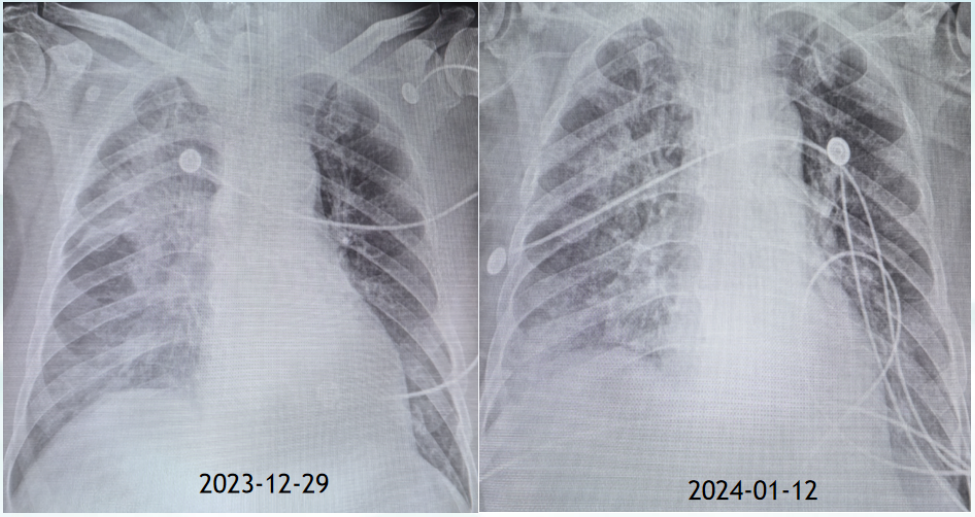

2024年112气管插管已2周,虽然感染逐渐得到控制,但脱机困难,于是行气管切开治疗患者消化道出血控制后继续予肠内营养积极进行康复训练促进呼吸肌及肢体功能的恢复。期间进行间断血滤维持肾功能

图片

19  患者胸片变化情况